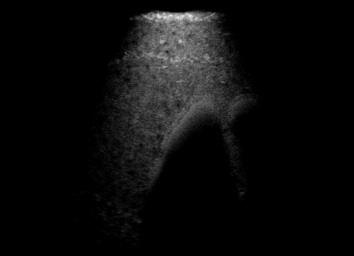

Real in-vivo images. 22 ultrasound sequences were collected using a GE Voluson E8 machine during standard fetal screening exams of 8 patients. Each sequence is several seconds long. We extracted all 4427 frames and resize them to , see Fig. 2 for some examples. The resulting image set was randomly split into training-validation-test sets by a 80-10-10% ratio.